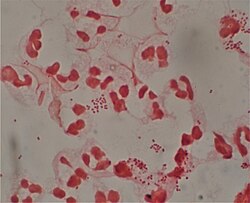

There are broadly speaking two different types of cell wall in bacteria, that classify bacteria into Gram-positive bacteria and Gram-negative bacteria. The names originate from the reaction of cells to the Gram stain, a long-standing test for the classification of bacterial species.[82]

Gram-positive bacteria possess a thick cell wall containing many layers of peptidoglycan and teichoic acids. In contrast, Gram-negative bacteria have a relatively thin cell wall consisting of a few layers of peptidoglycan surrounded by a second lipid membrane containing lipopolysaccharides and lipoproteins. Most bacteria have the Gram-negative cell wall, and only members of the Bacillota group and actinomycetota (previously known as the low G+C and high G+C Gram-positive bacteria, respectively) have the alternative Gram-positive arrangement.[83] These differences in structure can produce differences in antibiotic susceptibility; for instance, vancomycin can kill only Gram-positive bacteria and is ineffective against Gram-negative pathogens, such as Haemophilus influenzae or Pseudomonas aeruginosa.[84] Some bacteria have cell wall structures that are neither classically Gram-positive or Gram-negative. This includes clinically important bacteria such as mycobacteria which have a thick peptidoglycan cell wall like a Gram-positive bacterium, but also a second outer layer of lipids.[85]

The Gram stain, developed in 1884 by Hans Christian Gram, characterises bacteria based on the structural characteristics of their cell walls.Lua error: Internal error: The interpreter exited with status 1.Lua error: Internal error: The interpreter exited with status 1.[82] The thick layers of peptidoglycan in the "Gram-positive" cell wall stain purple, while the thin "Gram-negative" cell wall appears pink.Lua error: Internal error: The interpreter exited with status 1.Lua error: Internal error: The interpreter exited with status 1. By combining morphology and Gram-staining, most bacteria can be classified as belonging to one of four groups (Gram-positive cocci, Gram-positive bacilli, Gram-negative cocci and Gram-negative bacilli). Some organisms are best identified by stains other than the Gram stain, particularly mycobacteria or Nocardia, which show acid fastness on Ziehl–Neelsen or similar stains.[181]